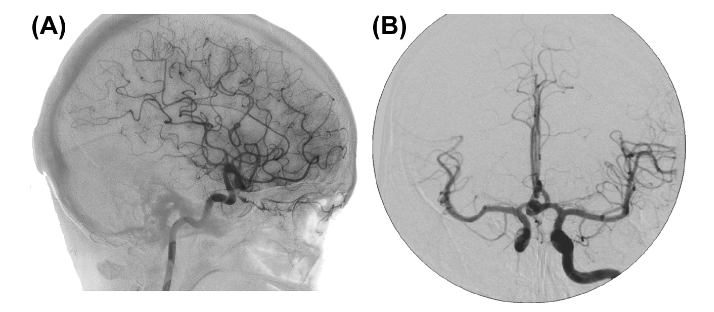

==Cerebral Angiography (aka an angiogram)==

An X-ray of the blood vessels.

It’s used to look for changes in the blood vessels, such as:

- Ballooning of a blood vessel (aneurysm)

- Narrowing of a blood vessel (stenosis)

- Blockages

General process:

a catheter (a tube inserted into the bladder) is inserted into an artery

- usually in the groin

the contrast dye is injected, followed by a series of X-rays

These x-ray images show the arteries, veins, capillaries, and blood flow in the brain